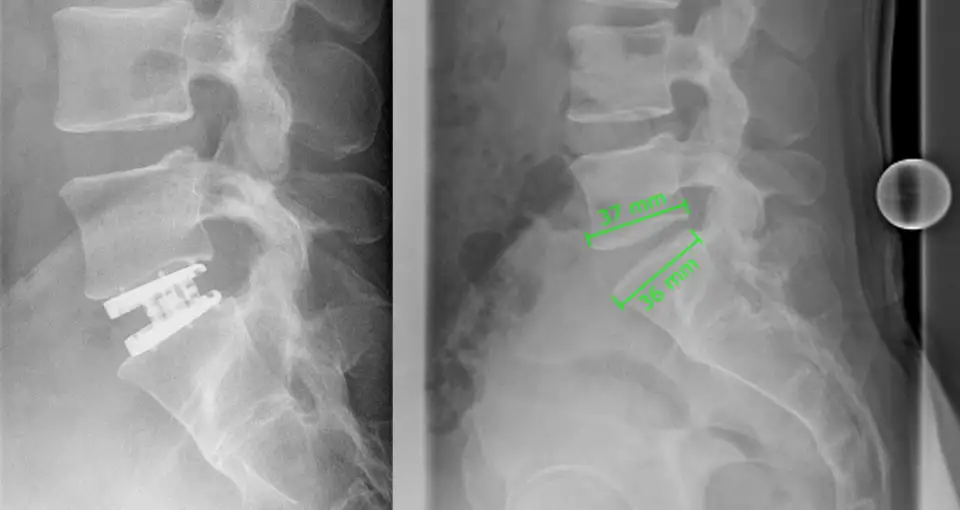

Loriston F., geboren 1976, möchte seine Erfahrungen mit Dr. Biren Desai und seinem Team aus Köln teilen. Die Operation in der Etage L4/5 und L5/S1 mit künstlicher Bandscheibenprothese (ADR) fand im Juli 2019 statt. Eine weitere Patienteninformation über den Prozess.

More than five years after the surgery, the patient is living an active and fulfilling life again. The debilitating nerve pain that once dominated everyday life is gone, mobility has been preserved, and long periods of sitting, traveling, hiking, and physical activity are once again possible. Follow-up imaging confirms that the ESP-LP artificial disc remains well positioned and that the adjacent disc is healthy.